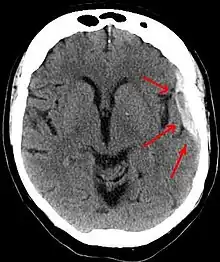

Chronic subdural after treatment with burr holes

It is important that a person receive medical assessment, including a complete neurological examination, after any head trauma. A CT scan or MRI scan will usually detect significant subdural hematomas.

Treatment of a subdural hematoma depends on its size and rate of growth. Some small subdural hematomas can be managed by careful monitoring as the blood clot is eventually resorbed naturally. Others can be treated by inserting a small catheter through a hole drilled through the skull and sucking out the hematoma.